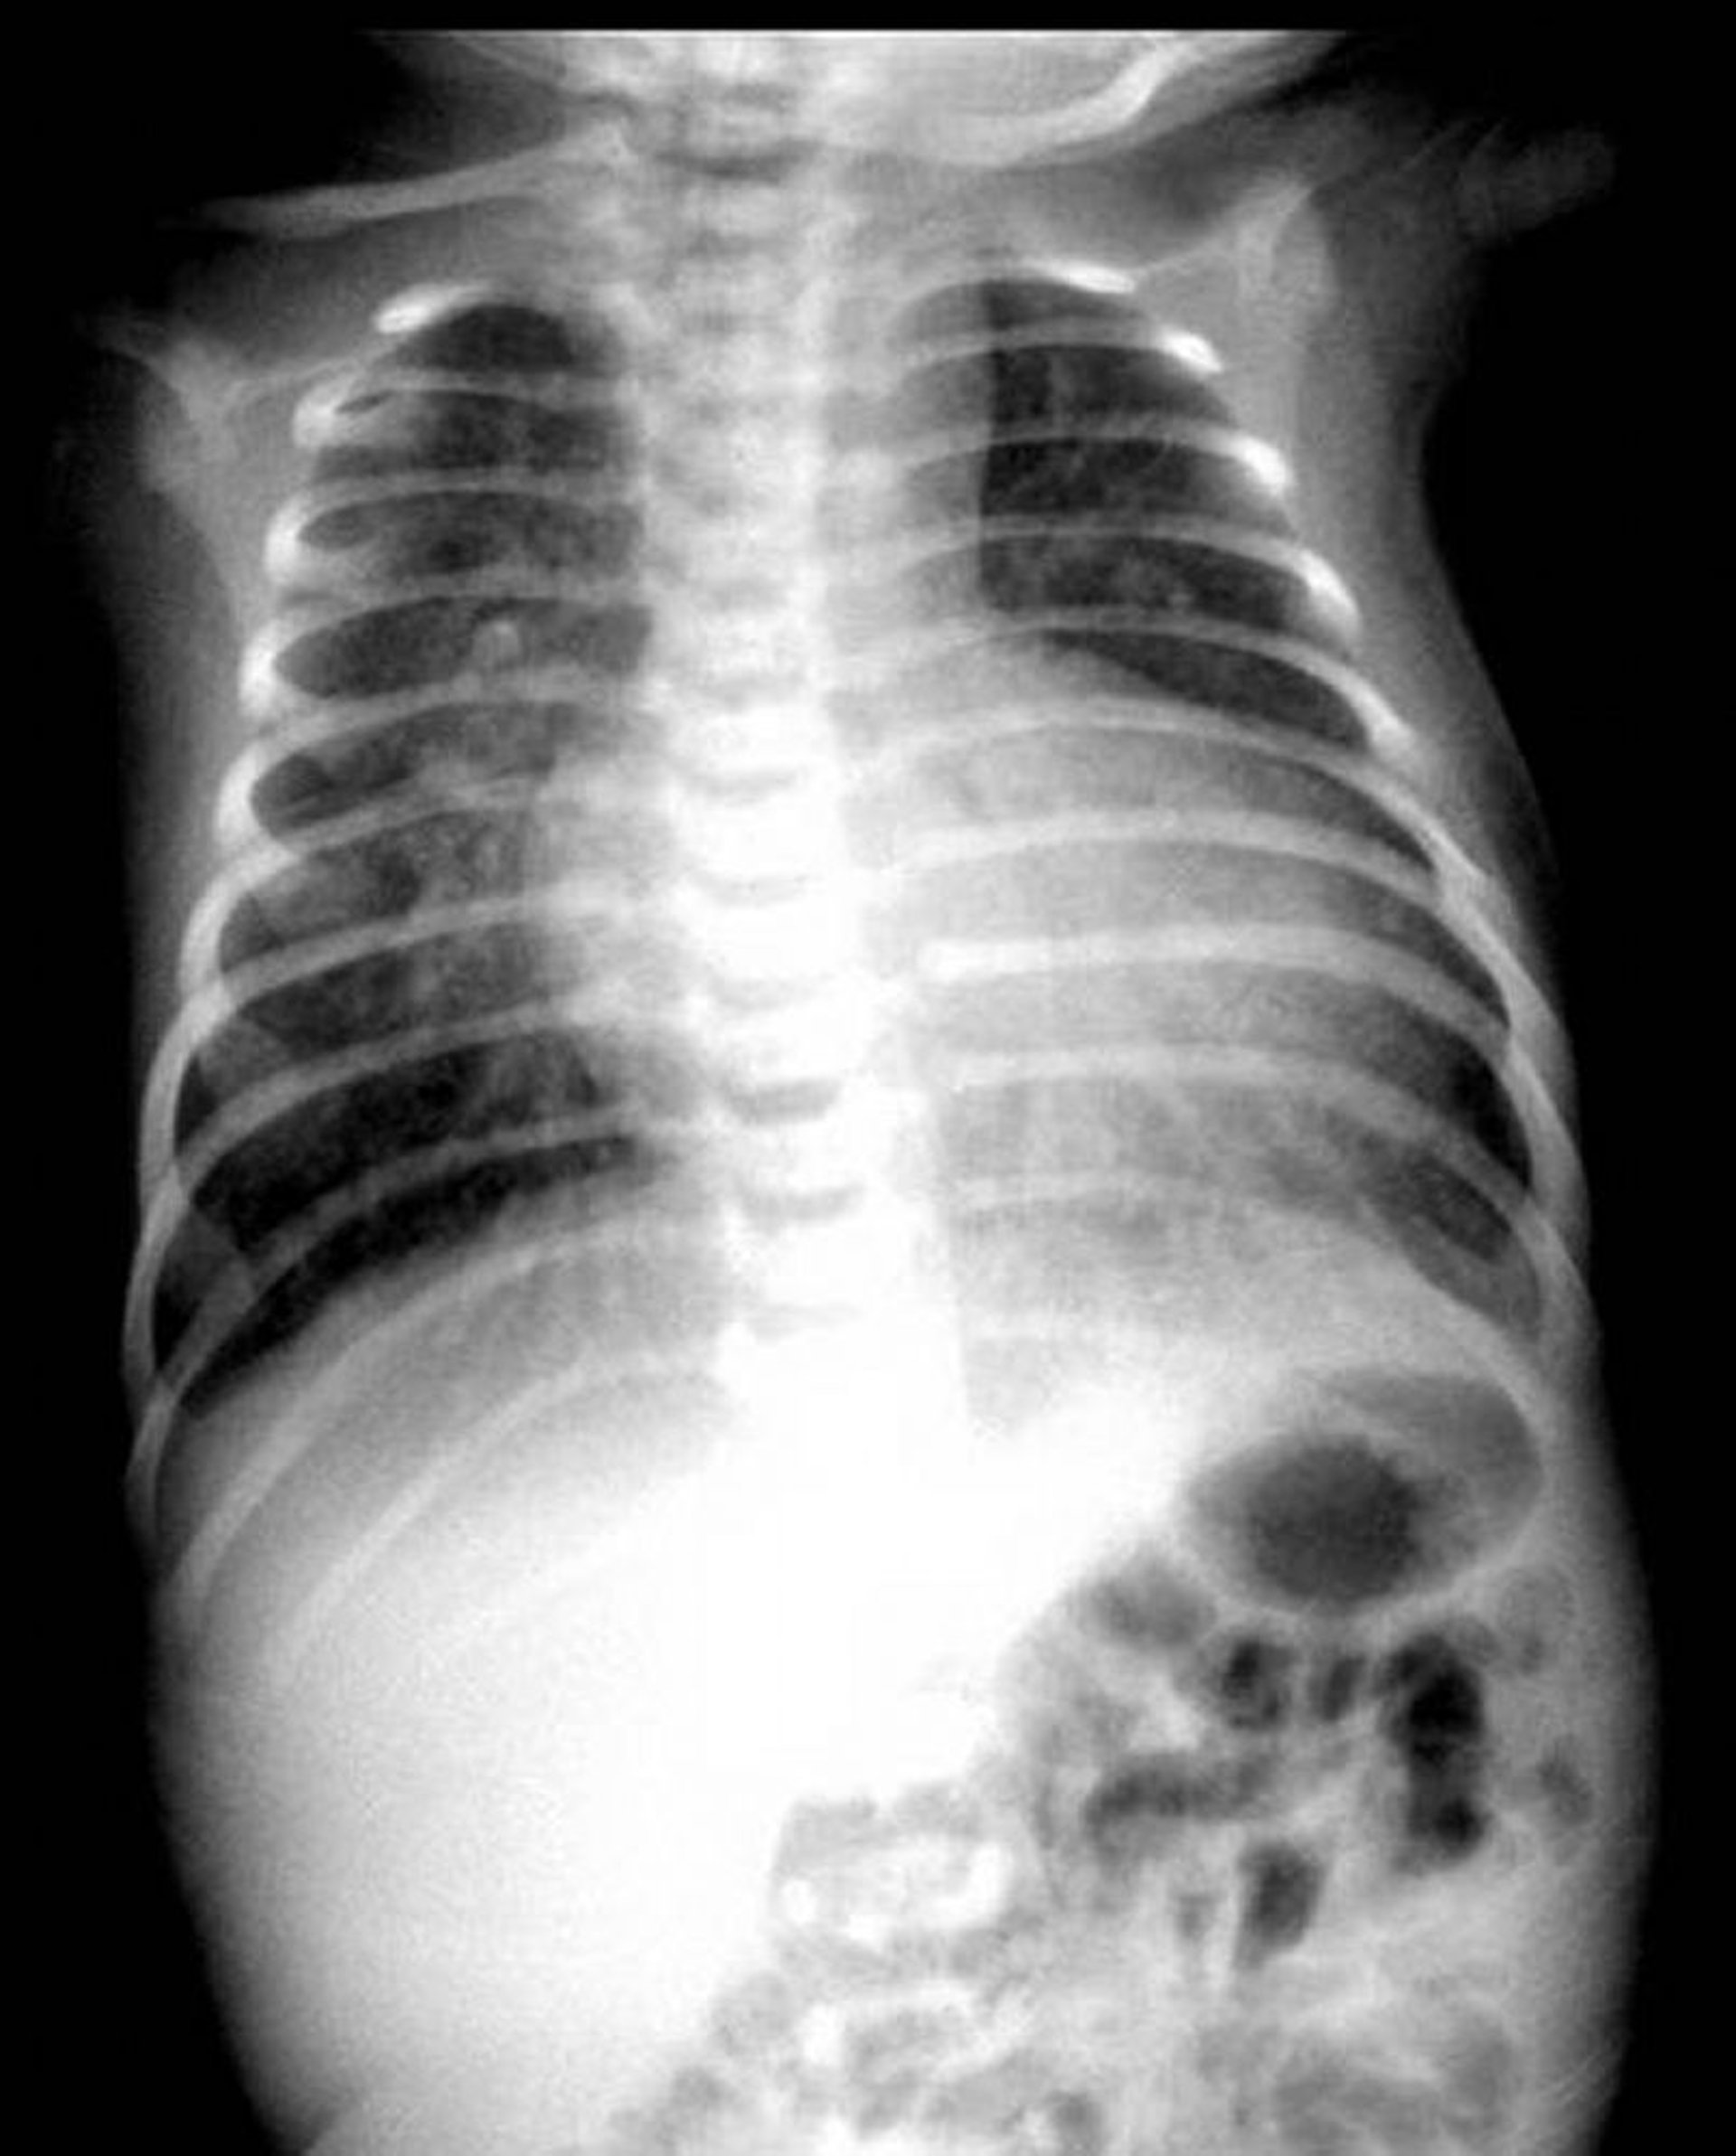

On chest x-ray, the cardiac shadow may have the classic egg-on-a-string appearance with a narrow upper mediastinum. ECG shows right axis deviation and right ventricular hypertrophy but may be normal for a neonate.